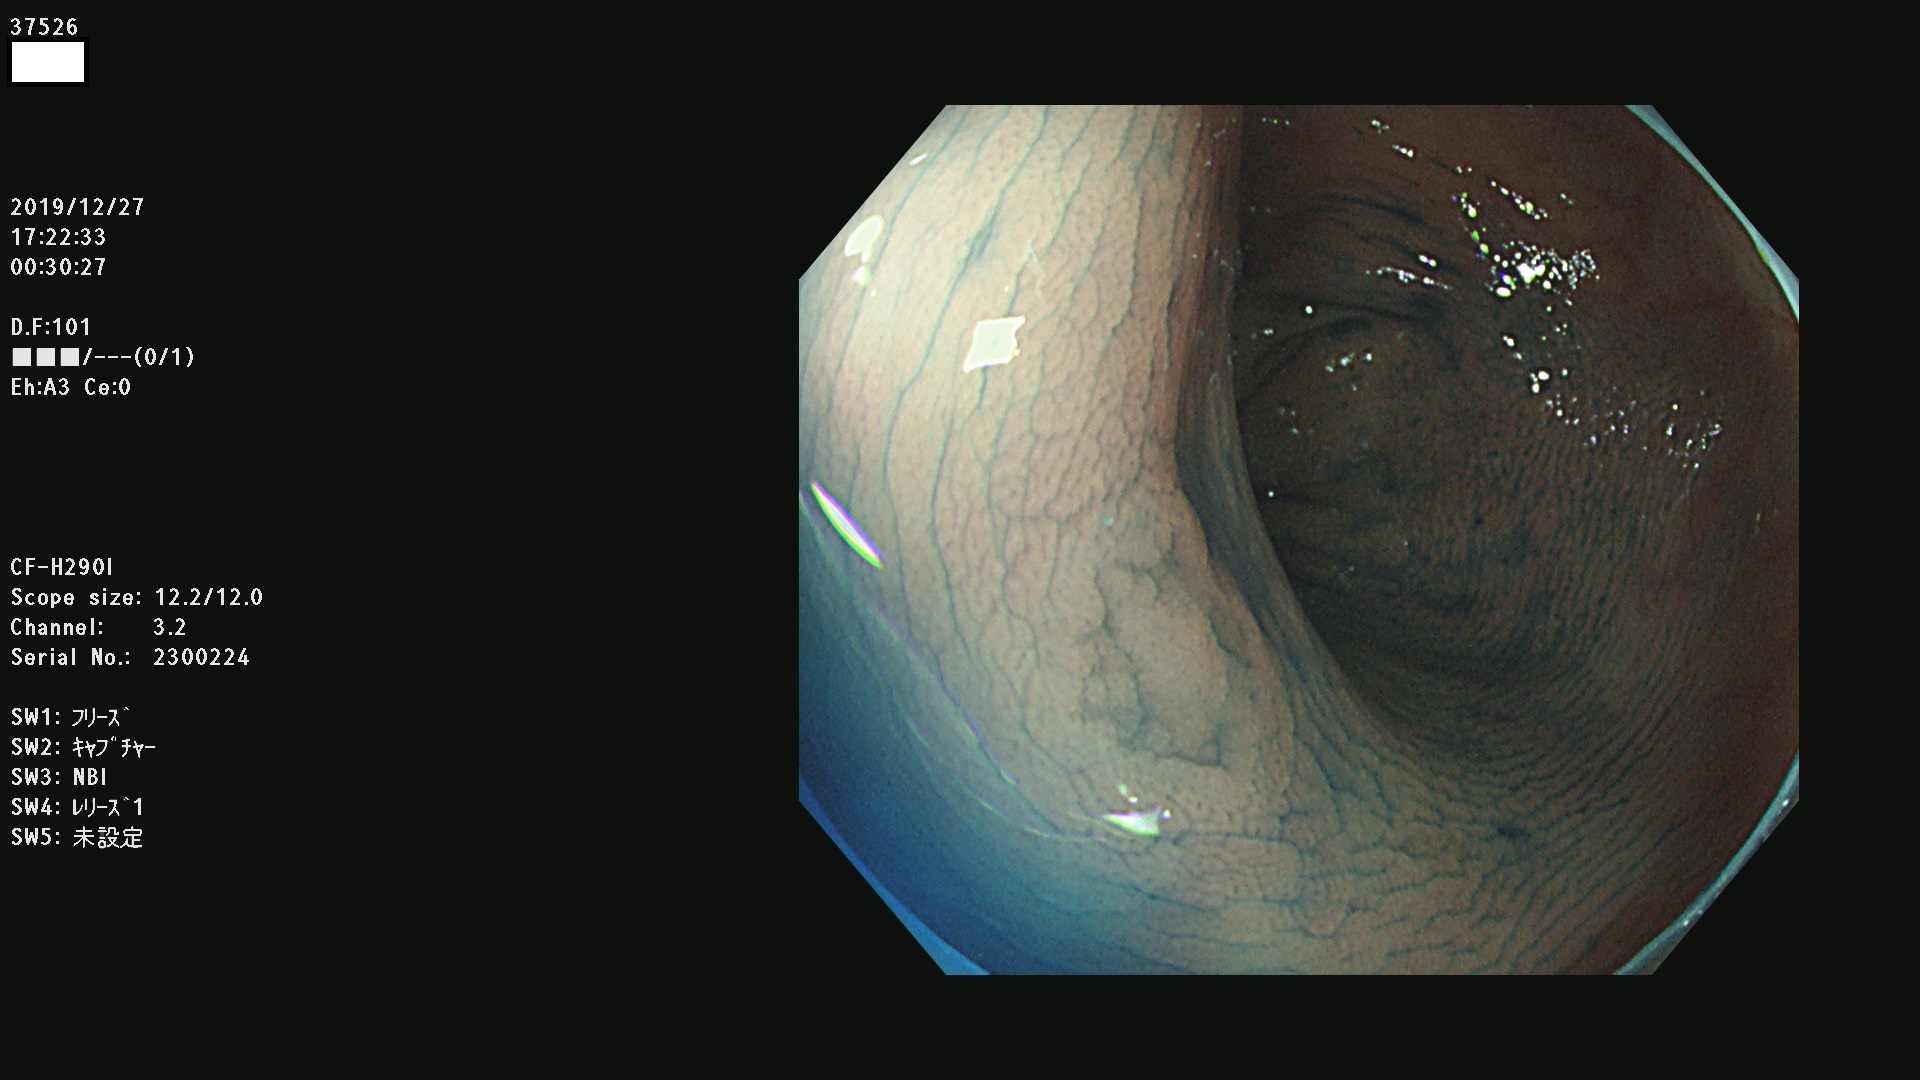

腺腫発見率 67 % (カルテ番号 37500〜37599の100名の方の検査結果で集計)大腸癌検診最新情報

以下のカルテ番号の方に腺腫(Adenoma,Group3〜5)が見つかりました(集計法)

37500 37502 37503 37505 37508 37509 37510 37511 37512 37513 37514 37517 37519 37520 37521 37525 37526(SSAPのみ) 37527 37528 37529 37531 37532 37533 37534 37536 37538(SSAPのみ) 37539 37541 37542 37543 37547 37548 37549(SSAPのみ) 37550 37552 37555 37556 37561 37562 37563(SSAPのみ) 37564 37565 37566 37567 37568 37570 37571 37572 37573 37574 37575(SSAPのみ) 37576 37577 37579 37580 37582 37583 37586(SSAPのみ) 37587 37588(SSAPのみ) 37590 37593(SSAPのみ) 37594 37596 37597(SSAPのみ) 37598 37599

発見困難で危険性の高い平坦型病変(上記100名より抽出) ![]()